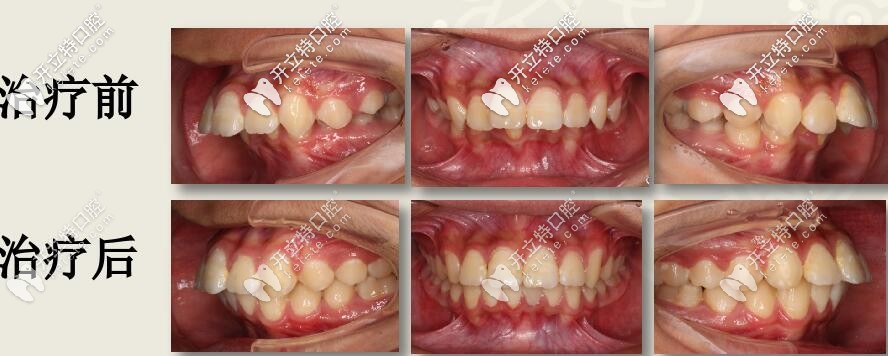

I期II期聯(lián)合矯治

1、I期:口外弓抑制上頜發(fā)育,肌激動(dòng)器促進(jìn)下頜發(fā)育

2、II期:全口直絲弓非拔牙矯治,排齊整平上下牙列

3、四眼簧改善下后牙舌傾異常,擴(kuò)弓提供排齊間隙

4、斜導(dǎo)導(dǎo)下頜向前,維持I期前移效果

5、改善面型、改善咬合關(guān)系

矯治時(shí)間:27個(gè)月

結(jié)束后,牙列整齊,深復(fù)蓋明顯改善。

本案例,用到了口外弓、肌激動(dòng)器、四眼簧擴(kuò)弓、斜導(dǎo)工具

其中肌激動(dòng)器,其實(shí)就是功能矯治器,生長(zhǎng)發(fā)育,可以考慮使用功能性矯治器,可緩解肌肉緊張,改善頦部形態(tài)。

斜導(dǎo)就是導(dǎo)下頜向前的工具。